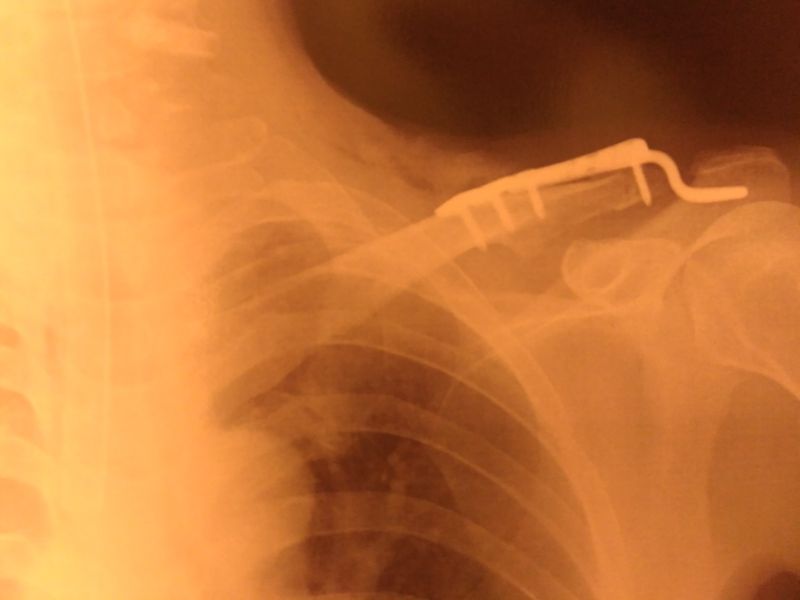

鎖骨手術から1週間経過

未だ、痛み止め無しでは生活できないほど痛い(;´Д`)

そして、今回はプレートを別の骨に引っ掛けている止めているんですが、その部分が特に痛くて殆ど腕を動かせません。。

これは想定外だった・・・

前回は2週間だか、2か月だか?痛みが続いたから、今回もまだ先は長い。

痛みで夜あまり寝られないのが辛い。。